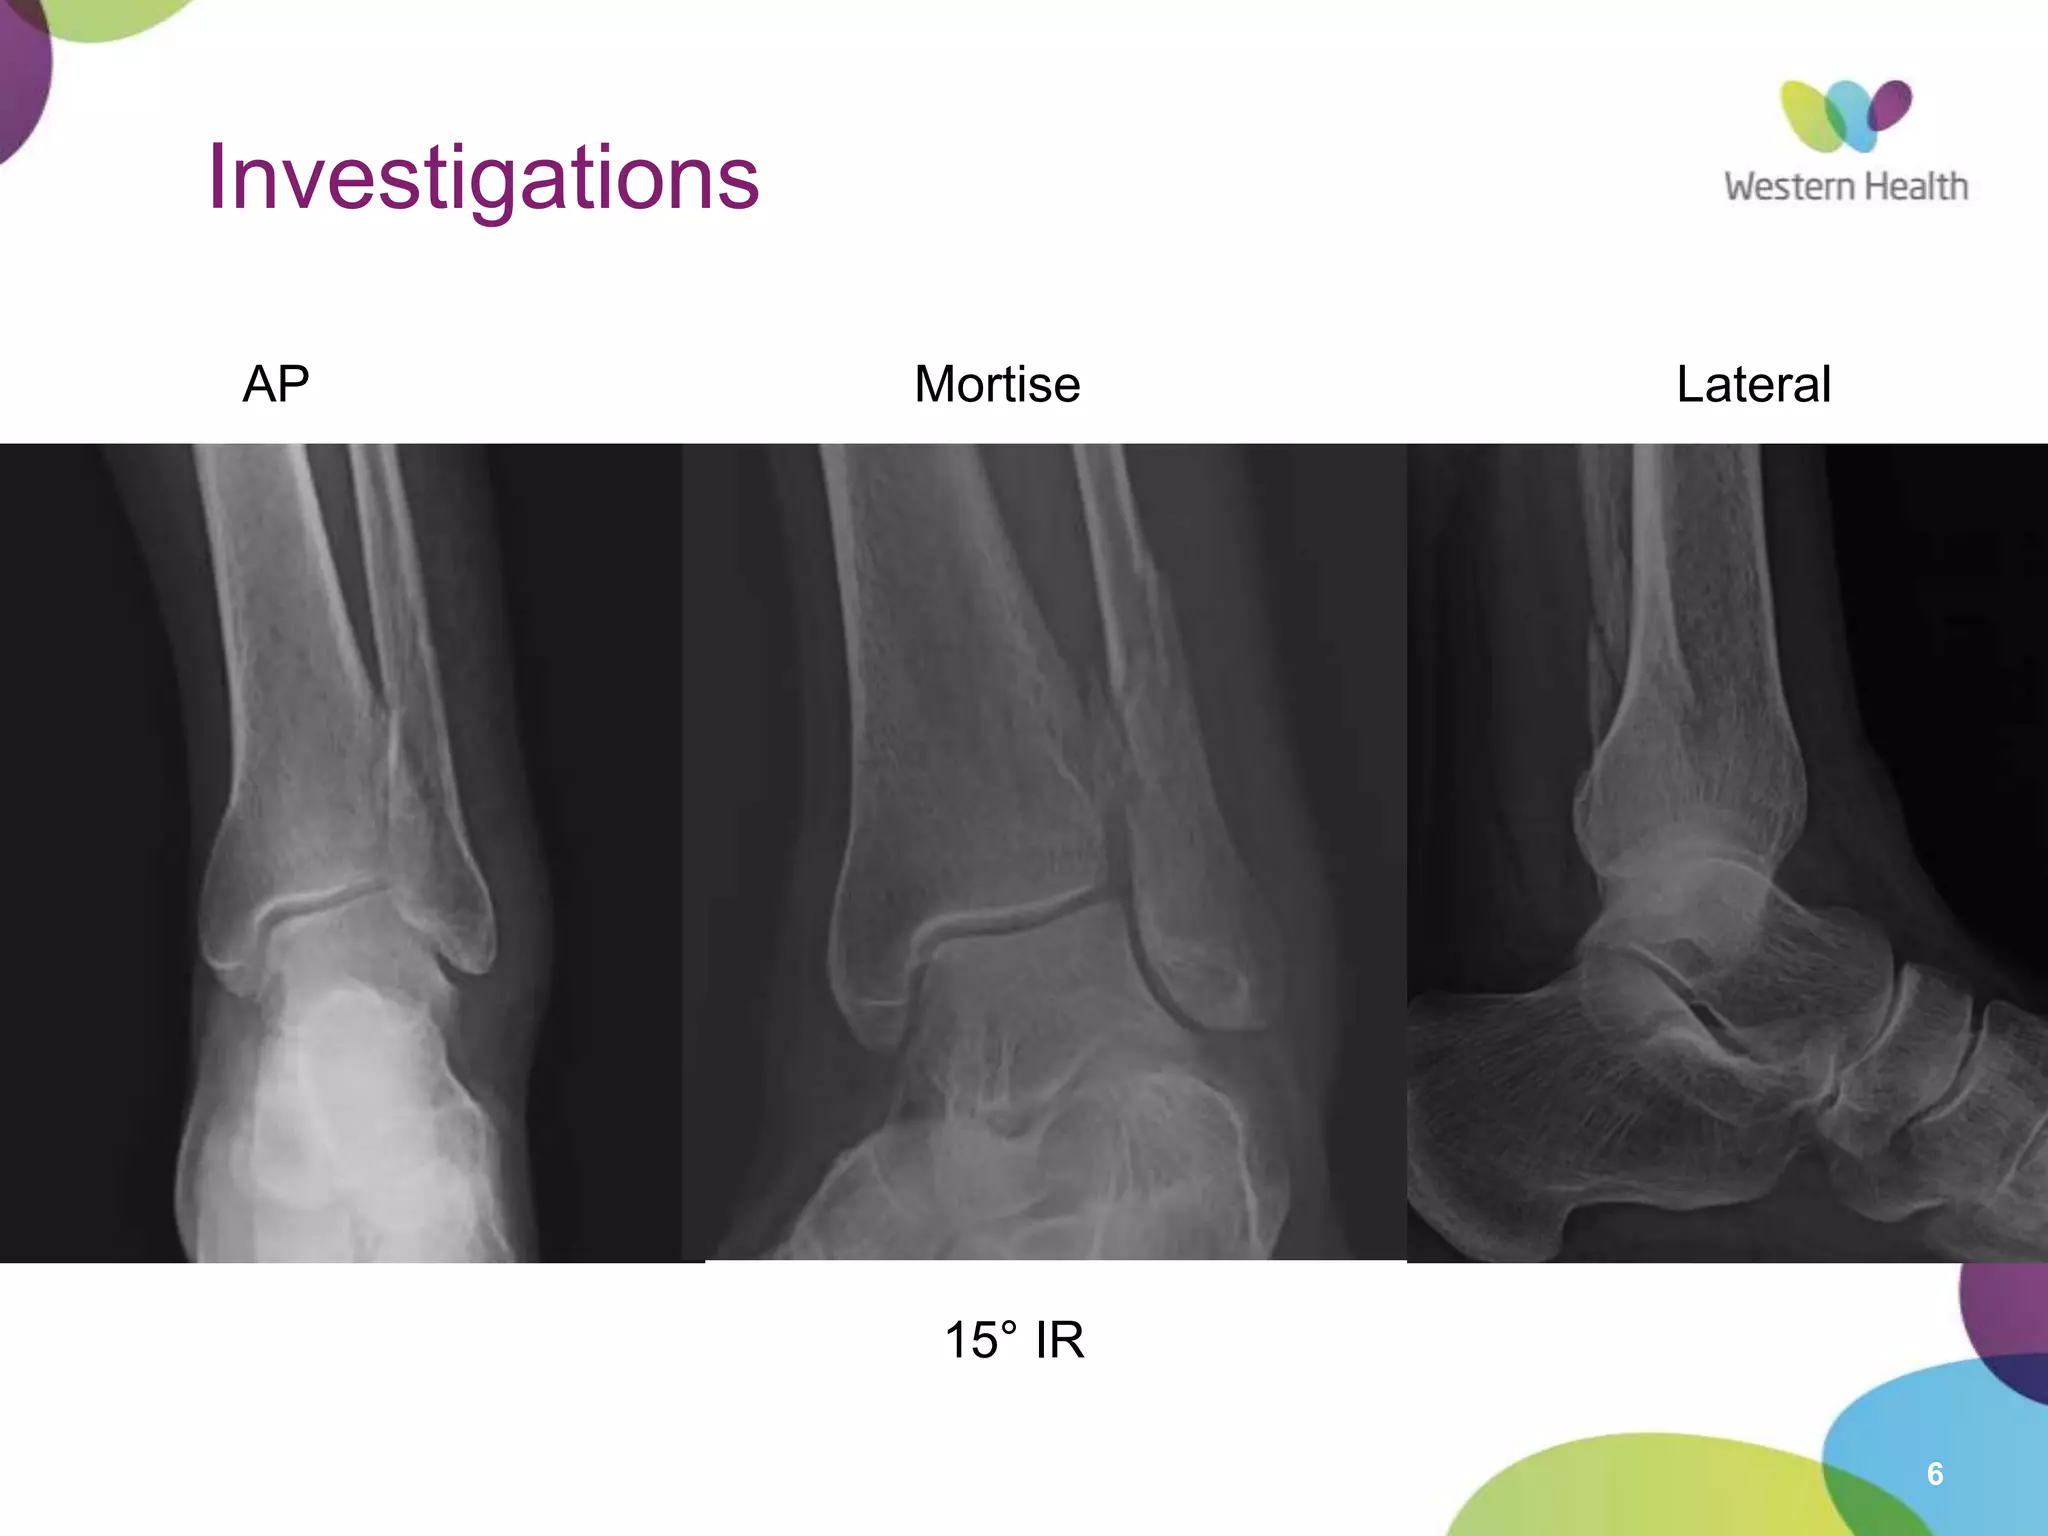

Investigations

AP Mortise Lateral

15° IR